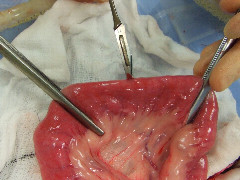

Kelly Bowlt

BVM&S, MRCVS

Kelly graduated from the University of Edinburgh in 2005 and after 18 months in small animal general practice, completed a rotating internship at the Royal Veterinary College and a three-year ECVS approved residency programme in Small Animal Surgery at the University of Bristol. Kelly joined the Animal Health Trust in 2011. She sits on committee for the Association of Veterinary Soft Tissue Surgeons (AVSTS) and her particular interests include minimally invasive surgery, trauma management and reconstructive/oncological surgery.